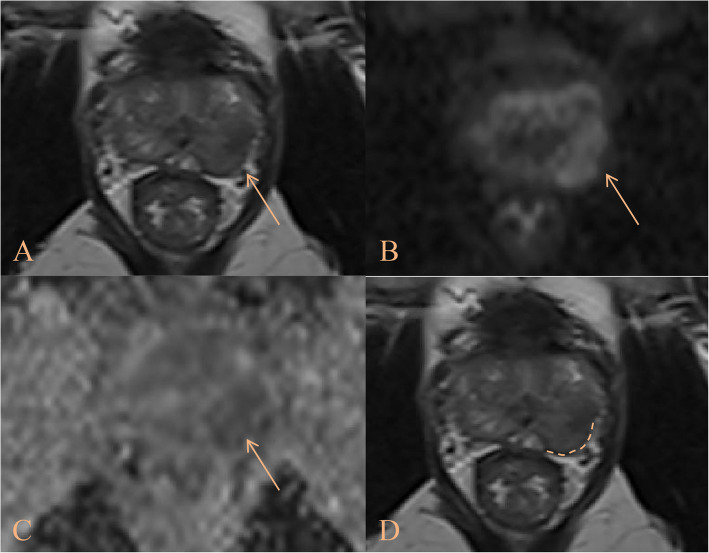

Methods: This retrospective study included 667 PCa patients divided into a derivation cohort and two validation cohorts. Evaluated parameters comprised prostate-specific antigen density (PSAD), curvilinear contact length (CCL), lesion longest diameter (LD), National Cancer Institute EPE grade (NCI_EPE), International Society of Urological Pathology grade (ISUP), and other relevant variables. Independent predictors were identified through univariate and multivariate regression analysis to construct a logistic model. Coefficients from this model were then weighted to establish a scoring system. The predictive performance of the NCI_EPE, logistic model, and scoring system was systematically evaluated and compared. Finally, the scoring system was stratified into four distinct risk categories.

Results: Multivariate analysis identified NCI_EPE, PSAD, CCL/LD, and ISUP as independent predictors of EPE. In the derivation and validation cohorts, the scoring system demonstrated robust predictive accuracy for EPE, with AUCs of 0.849, 0.830, and 0.847, respectively. These values outperformed the NCI_EPE (Derivation cohort: 0.849 vs. 0.750, P < 0.003, Validation cohort 1: 0.830 vs. 0.736, P = 0.138, Validation cohort 2: 0.837 vs. 0.715, P = 0.003) and were comparable to the logistic model (Derivation cohort: 0.849 vs. 0.860, P = 0.228, Validation cohort 1: 0.830 vs. 0.849, P = 0.711, Validation cohort 2: 0.837 vs. 0.843, P = 0.738). Decision curve analysis revealed higher net clinical benefit for both the scoring system and logistic model compared to the NCI_EPE. Risk stratification using the scoring system categorized patients into four tiers: low (0-3), intermediate-low (4-6), intermediate-high (7-9), and high risk (10-12) with corresponding mean EPE probabilities of 9.9%, 26.0%, 52.0%, and 85.0%. These probabilities closely aligned with observed pT3 incidences in the derivation and validation cohorts.